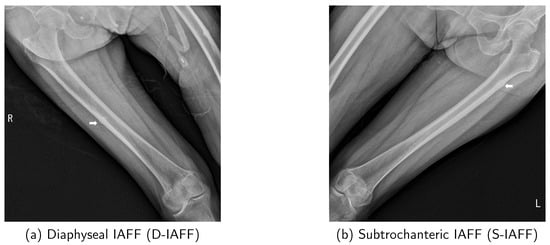

In the early stages preceding the occurrence of AFF, cortical buckling will develop in the lateral cortex of the femur due to repeated cycles of microfracture and healing [12]. This condition is termed Incomplete Atypical Femoral Fracture (IAFF). IAFF exhibits various characteristics and is classified based on its location as shown in Figure 1: Diaphyseal IAFF (D-IAFF), which occurs in the femoral shaft, and Subtrochanteric IAFF (S-IAFF), which occurs in the subtrochanteric region [13]. Although IAFF is a crucial precursor to AFF, it is often asymptomatic or presents with vague features, making detection difficult and often resulting in delayed diagnosis. As a precursor to AFF, the progression process from IAFF to AFF is illustrated in Figure 2. IAFF is typically diagnosed through bone scans [14] or Magnetic Resonance Imaging (MRI) [15]. However, these diagnostic methods have notable drawbacks, including high costs and time consumption. Furthermore, there remains the risk of misdiagnosis [14], which can lead to either unnecessary or delayed interventions, ultimately culminating in a complete fracture.